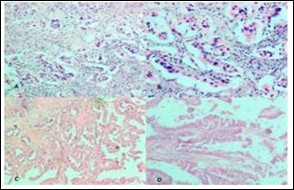

Figure 3.Photomicrograph showing A, Low power view of Adenocarcinoma Gall bladder; B, High power view shows attempted gland formation with moderate pleomorphismmoderately differentiated adenocarcinoma Gall Bladder; C, Low power view of Papillary carcinoma GB; D, High power view showing papillae with fibrovascular cores lined by malignant cells- Papillary carcinoma GB (H&E)